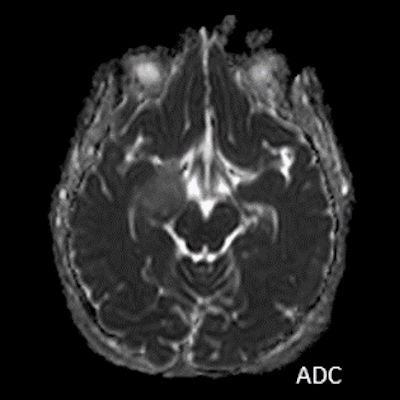

- B) Lezyon difüzyon görüntüde izo-hiperintens, ADC haritalamada hafif hiperintens izlenmiş olup (oklar) diffüzyon kısıtlılığı göstermemektedir. Lezyonun anterior kesiminde kontrastlı serilerde yamalı kontrast tutulumları (oklar) mevcuttur. MR spektroskopide lezyon düzeyinden elde olunan multivoksel görüntülerde kolin pikinde artış ve NAA da azalma (oklar) dikkati çekmektedir. Kolin/kreatinin oranı 1.76 olarak ölçülmüştür.

- MRG: T1A serilerde solid komponent izo-hipointens, T2A serilerde genellikle hiperintens sinyalde görülür. Peritümöral T2/FLAIR hiperintens kitle ödemi oldukça nadirdir. T1 C+ görüntülerde solid komponentte değişken oranda kontrastlanma ,T2*(SWI) serilerde eğer kalsifikasyon eşlik etmekteyse buna bağlı blooming artefaktları görülebilir.